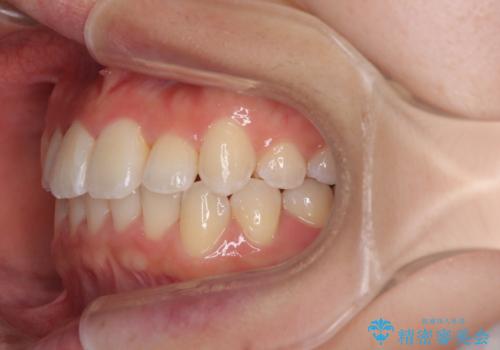

前歯のクロスバイト 裏側に隠れた歯をワイヤー装置で短期間治療

- 上顎前歯のクロスバイトを気にして来院された患者様です。

装置の外見を気にしていましたが、短期間で治療を終えることができるだろうと伝えると、安価であるメタルブラケットを選択されました。

想定通り、1年強で綺麗に仕上げることができました。